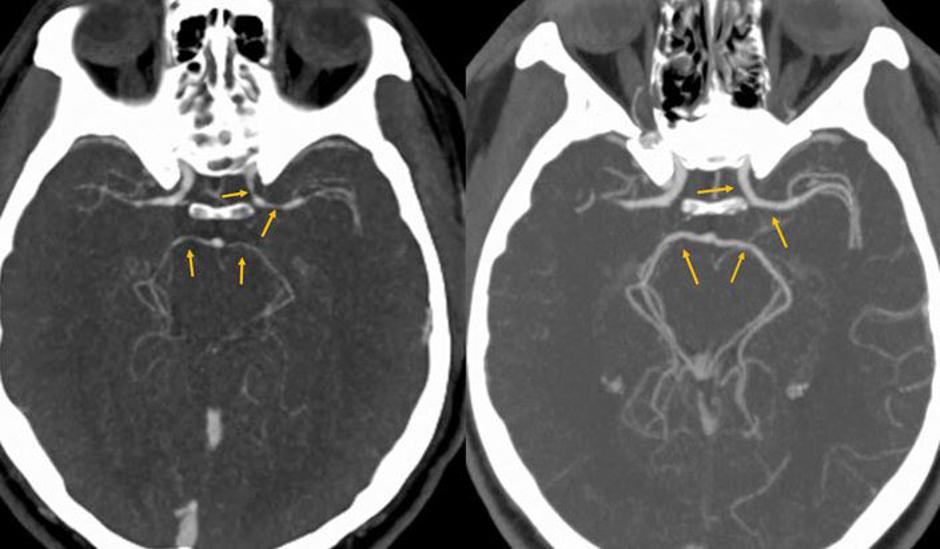

Računalniška tomografija glave pokazala, da so se moškemu močno zožile arterije.

Prvi pregledi niso odkrili ničesar nenavadnega. Računalniška tomografija glave pa je pokazala, da so se moškemu močno zožile arterije. Po zdravljenju, ki je vključevalo hidratacijo in uživanje protibolečinskih tablet, so se glavoboli končali. Pet dni kasneje so slike možganov pokazala, da so arterije vrnile v običajno velikost.